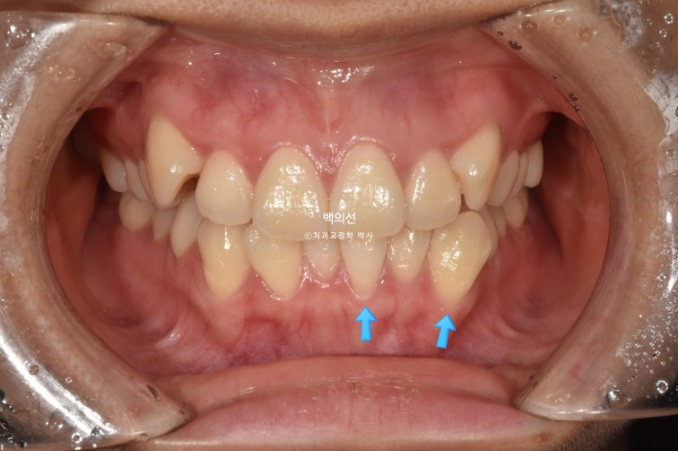

23년 7월 교정을 위해 내원한 환자분입니다.

덧니가 심한 편 입니다.

잇몸이 얇아서 20대 초반의 나이임에도 불구하고 덧니를 포함한 일부 치아의 잇몸이 내려가 있습니다.

군데군데 잇몸이 내려가 뿌리 노출된 부분들이 있습니다.

교정치료로 한 번 내려간 잇몸이 다시 차오르지는 않지만 , 발치교정을 통해 최소한 뿌리를 안쪽으로 넣어주어

더 이상 내려가는 것을 막아줄 순 있습니다.

덧니 펼 공간이 많이 필요하고 잇몸도 얇아 비발치로 치료 시 잇몸이 더 내려갈수도 있는 상태입니다.